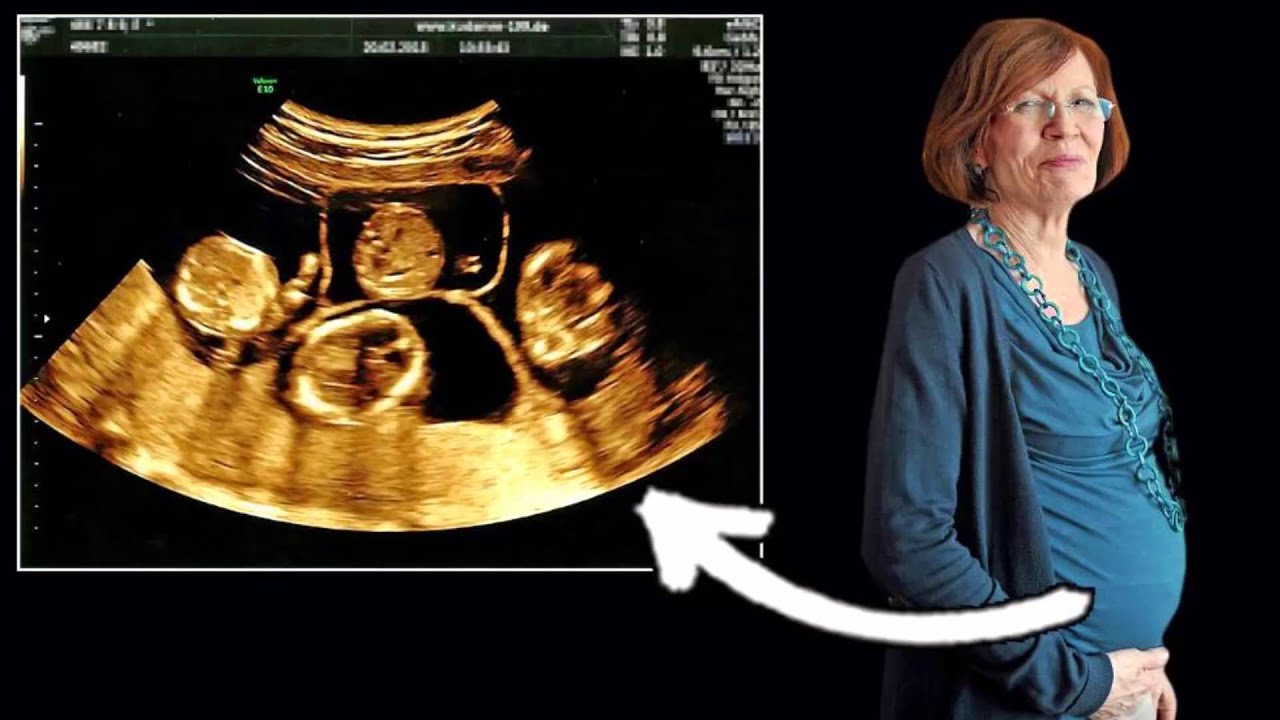

65 лет забеременела

65 лет забеременела 106 фото